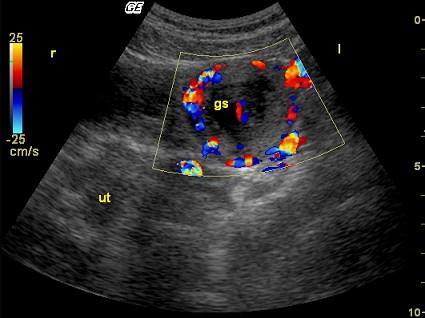

问题 女性,22岁,停经40天,尿HCG阳性。超声检查见图,最可能的诊断是 ( )

选项 A、黄体囊肿 B、正常声像图 C、畸胎瘤 D、宫外孕 E、炎性包块

答案 D